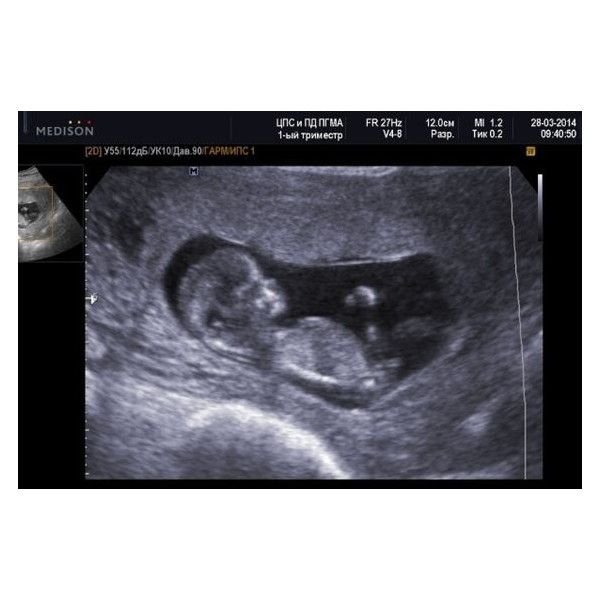

За какие-то 12 недель из одной клеточки получается маленький человечек! Ваш кроха уже умеет морщить губки, закрывать и открывать глазки, сжимать и разжимать ручки в кулачок и даже поворачивать головку. У малыша уже разделились пальчики рук и ног. Он также научился открывать ротик и глотать околоплодную жидкость.

Продолжает развиваться и нервная система. Кроха активно шевелится, только вы это почувствуете приблизительно через месяц. А сейчас уже можно четко услышать биение маленького сердечка с помощью допплера. Кроме того, кроха уже все слышит и видит! Разве это не чудо?

Для врача первое УЗИ очень важно с медицинской точки зрения. Его проводят (на 11-14 неделях) как часть пренатального генетического скрининга для определения количества плодов, измерения воротниковой зоны и выявления грубых пороков развития. Во время УЗИ можно врач подсчитает, сколько ударов делает сердечко крохи (норма — 130–150 сокращений в минуту), а вы увидите, как он двигает ручками и ножками, сжимает кулачки, поворачивает головку, открывает ротик, глотает и даже пробует сосать свой собственный пальчик. Также на УЗИ фиксируют размеры плода и по ним судят о моменте зачатия.

В 12 недель у ребенка формируются ногти, и лицо теперь выглядит как человеческое. Плод полностью сформирован, все его органы хорошо развиты.

Ребенок может быть около 60 мм в длину и весить около 14 граммов.Малыш шевелится, хотя мама еще не может этого почувствовать. Хрящ, который развился у ребенка, теперь начинает превращаться в кость.